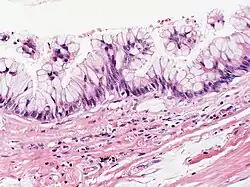

Atypical goblet cells with focal tufting. The classification of these rare neoplasms is difficult and controversial. There appears to be a spectrum of mucinous cystic tumors ranging from those that are obviously benign (benign epithelium and no tumor invasion into surrounding lung) to those that exhibit invasion into surrounding lung tissue and are, therefore, malignant. In between is a group of neoplasms that exhibit epithelial atypia but no tumor invasion into lung tissue and the malignant potential of these is uncertain. This case appears to fall into that category. Focal cyst rupture with extravasation of mucin into surrounding lung tissue may occur with all types of mucinous cystic tumors.